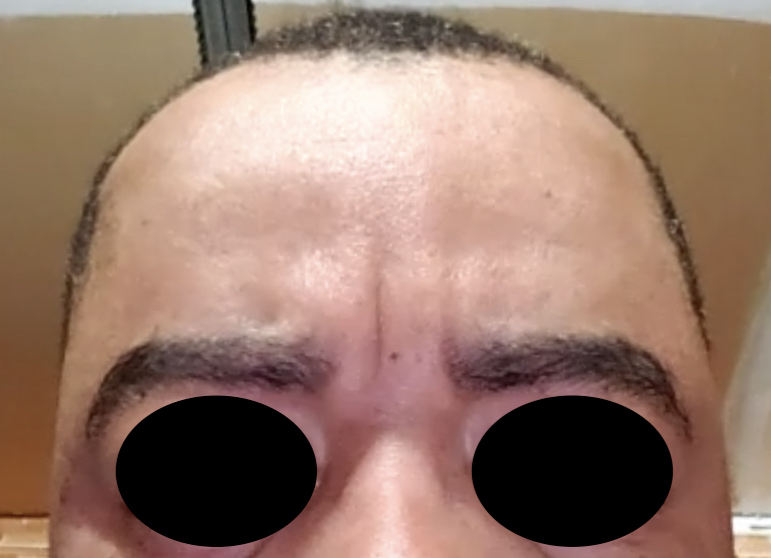

Patient 28

Desire for rounder shape to the top of the head from a congenital parasagittal deficiency skull shape.

Custom skull implant designed to fill in the parasagittal deficiencies.

Desire for rounder shape to the top of the head from a congenital parasagittal deficiency skull shape.

Custom skull implant designed to fill in the parasagittal deficiencies.